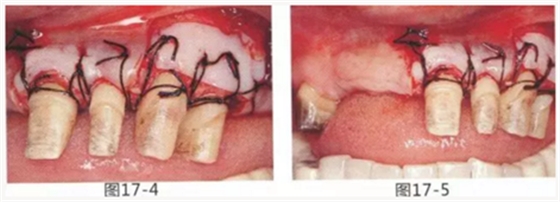

圖17-4 左上1,2進行齦瓣根尖側(cè)轉(zhuǎn)移,左上3,4進行游離牙齦移植,在去除牙周袋的同時獲取附著齦。

圖17-5 牙周治療完成后的正面照。左上3,4部位處游離齦移植片的上端通過骨膜縫合固定在頰側(cè)嵴頂部。這樣可以使其愈合效果與齦瓣根尖側(cè)轉(zhuǎn)移相同。